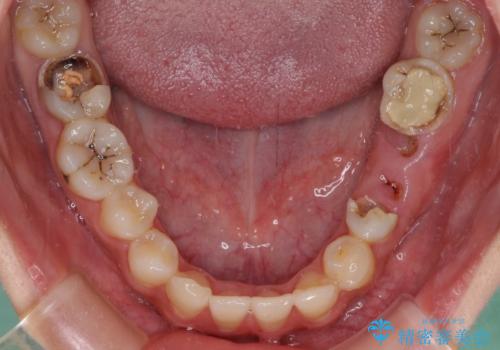

むし歯だらけの奥歯 セラミッククラウンによるむし歯治療

- 奥歯のむし歯を気にして来院された患者様です。

痛みのある歯が多く、根管治療が必要と診断されました。

左下の歯は、クラウンを装着するために必要な高さが足りないため、歯冠長を延長するための外科処置を行うこととしました。

自身の口腔内への意識が高くなく、汚れが非常に多い方でした。